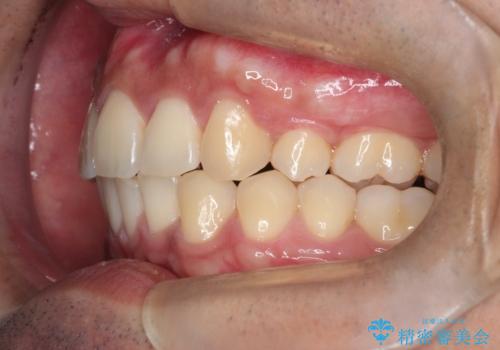

- 歯並びの凸凹を主訴に来院されました。

スペースが必要なため、抜歯を行なって治療を行いました。

奥歯の捻れが強く治療期間がかかりましたが、綺麗な仕上がりに満足していただきました。